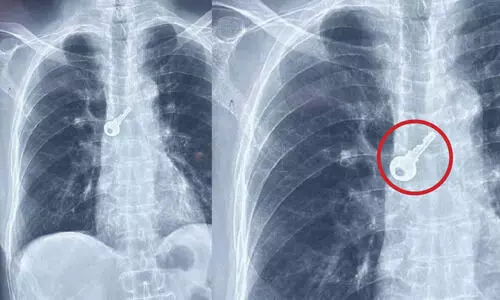

അമ്പലപ്പുഴ: വയോധികന്റെ ശ്വാസനാളത്തിൽ കുടുങ്ങിയ താക്കോൽ ബ്രോങ്കോസ്കോപ്പി പരിശോധനയും...